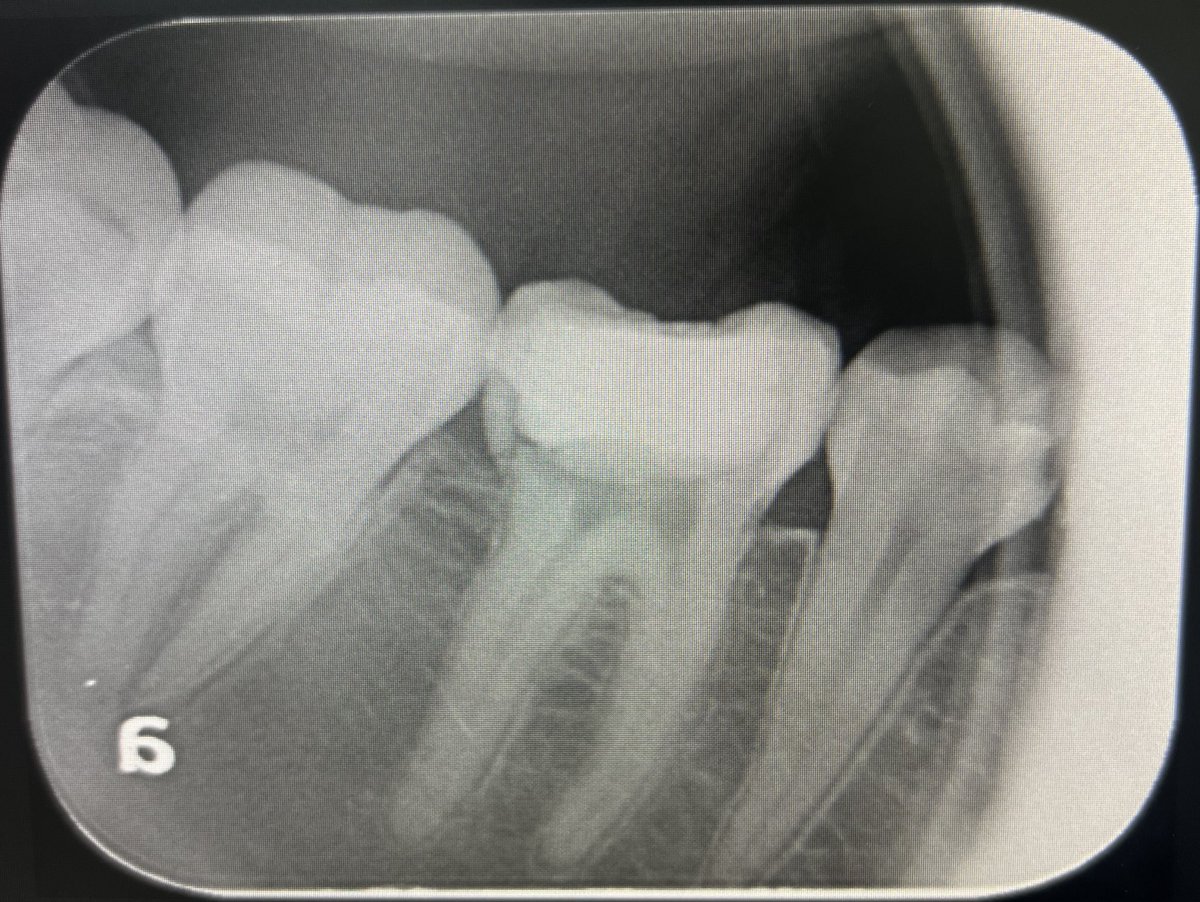

حالة جديدة اليوم ❤️

Root Canal Treatment for #36

The patient complained of severe pain,after examination we decided to do RCT.

Dx: SIP,NAP

ML wall is replaced then started RCT.

Single Cone and BC Sealer are used